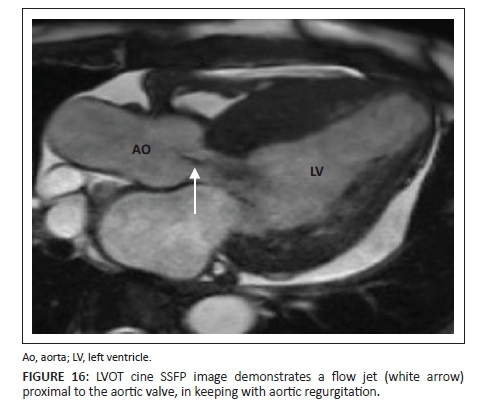

Regurgitation

Valvular regurgitation is seen as dephasing or as a flow jet proximal to the valve (Figure 16). With regurgitation, more severe disease results in a large opening which causes less dephasing and thus results in a less obvious jet.

Aortic and pulmonary valve regurgitation is normally measured directly with phase contrast images. By drawing a region of interest in the vessels, the forward volume and regurgitation volume can be measured and used to calculate the regurgitation fraction (regurgitation volume/forward volume × 100).11